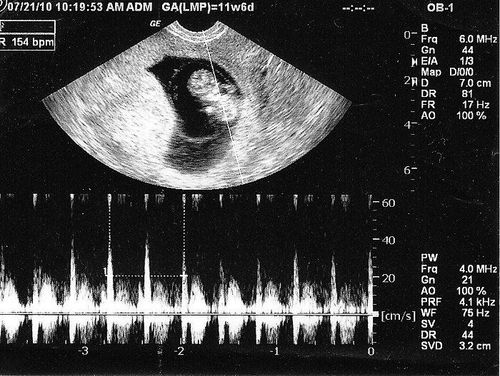

Using real-time two-dimensional imaging of the mother’s uterus, ultrasound detects the fetal heartbeat based on heart activity. Calculating gestational age from the last menstrual period places this detection at approximately 5 to 6 weeks of fetal age.Doppler signals can detect the blood flow from the fetal heart and large blood vessels after 6 weeks of pregnancy. From 20 weeks onward, the fetal heartbeat can be heard with a standard stethoscope. A progressively stronger heartbeat indicates a healthy and well-developing fetus.

From week 6 onward, the fetal heartbeat can be detected by ultrasound, based on the timing and development process. In some cases, detection may be delayed until week 8 due to miscalculations of the menstrual period or gestational age.